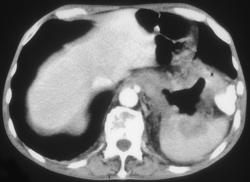

Gastric Varices